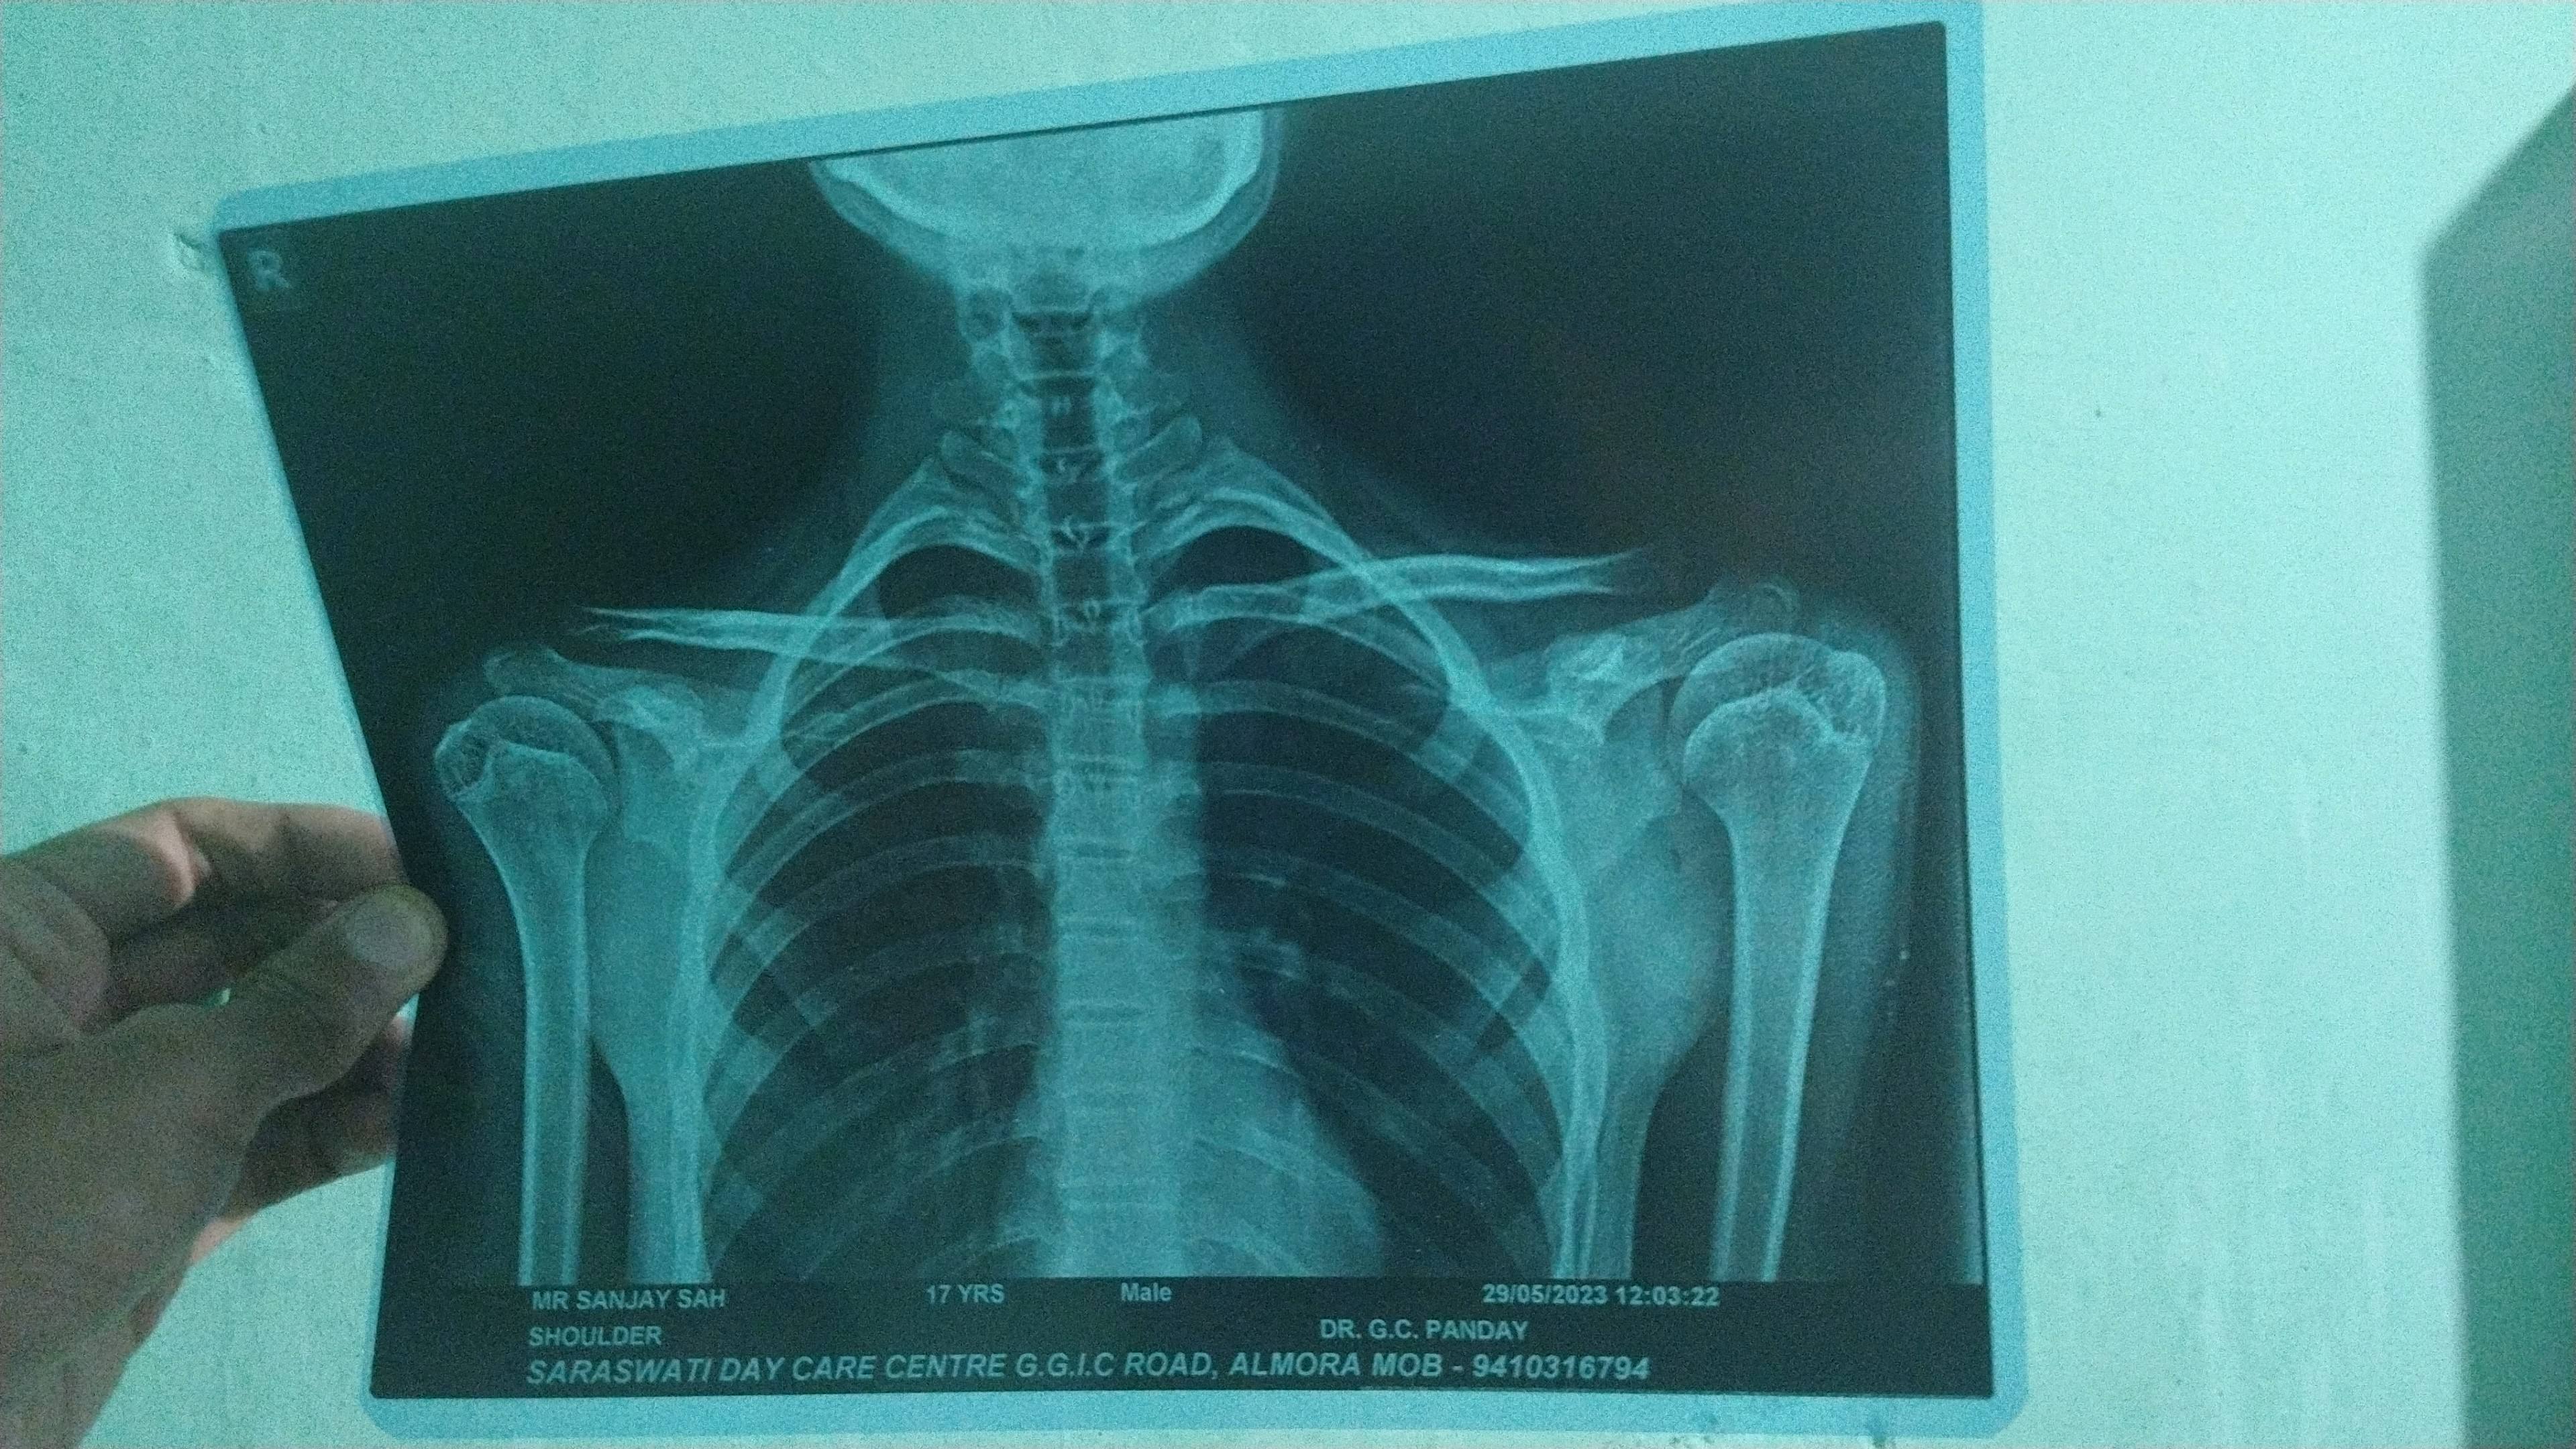

Hy sir mere hip joint me bhut pain hota h n thaig me 1 saal se bhut treatment lia but kuchh frk nhi pd raha h